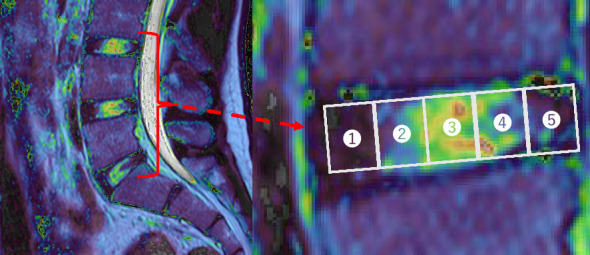

背景:跑步可以对椎间盘(IVDs)产生有益和有害的反应。为了更好地理解这些影响,我们研究了慢速跑步时负荷方向与跑步前后腰椎ivd T2时间快速变化之间的关系。方法:16名健康男大学生安装三轴加速器,在8 km/h的跑步机上跑1分钟。通过磁共振成像(MRI)测量运动前、运动后和运动后30分钟从L3/L4到L5/S1水平的3个腰椎T2时间。分析集中在每个光盘中的五个感兴趣的区域。结果:中外侧(x轴)方向加速度为0.23±0.06均方根,竖直(y轴)方向加速度为1.37±0.08,正前方(z轴)方向加速度为0.30±0.06。在T2弛豫时间和加速度之间观察到很强的相关性,特别是在z轴上。在L3/L4,后核呈正相关(r = 0.72, p=0.002, r2 = 0.59)。在L4/L5时,中央核呈正相关(r = 0.73, p=0.003, r2 = 0.49)。在L5/S1时,前纤维环呈负相关(r = -0.73, p=0.01, r2 = 0.48)。结论:前向负荷可能在ivd对奔跑的反应中起重要作用。

Background: Running can contribute to both beneficial and detrimental responses in the intervertebral discs (IVDs). To better understand these effects, we investigated the relationship between loading directions during slow running and the rapid changes in T2 times occurring in the lumbar IVDs before and after running. Methods: Sixteen healthy male students were fitted with a triaxial accelerator and ran on a treadmill at 8 km/h for 1 minute. Three lumbar T2 times from the L3/L4 to L5/S1 levels were measured before, immediately after, and 30 min postexercise via magnetic resonance imaging (MRI). The analysis focused on five regions of interest within each disc. Results: Acceleration was 0.23 ± 0.06 root mean square in the mediolateral (X-axis), 1.37 ± 0.08 in the vertical (Y-axis), and 0.30 ± 0.06 in the anteroposterior (Z-axis) direction. A strong correlation was observed between the T2 relaxation times and acceleration, particularly in the Z-axis. At L3/L4, a positive correlation was observed for the posterior nucleus (r = 0.72, p=0.002, R 2 = 0.59). At L4/L5, a positive correlation was observed for the central nucleus (r = 0.73, p=0.003, R 2 = 0.49). At L5/S1, a negative correlation was observed for the anterior annulus fibrosus (r = -0.73, p=0.01, R 2 = 0.48). Conclusion: These results suggest that anteroposterior loading may play a significant role in the response of the IVDs to running.